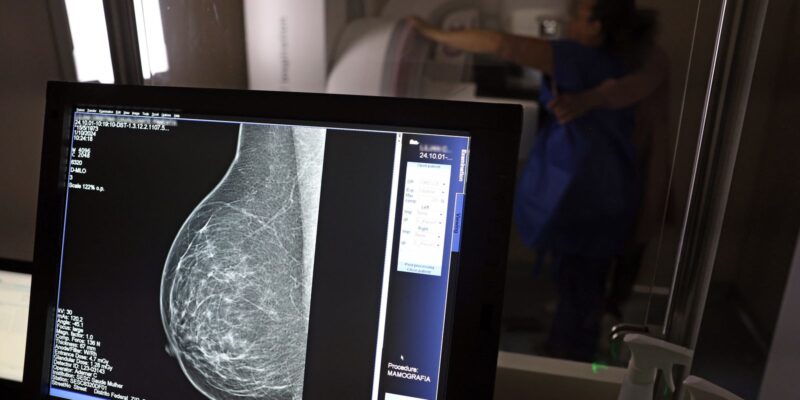

Em junho deste ano, 77.243 brasileiras aguardavam por uma mamografia no Sistema Único de Saúde (SUS). Santa Catarina é o estado com mais mulheres na fila de espera, cerca de 17 mil. Em seguida, aparecem São Paulo (15 mil) e Rio de Janeiro (12,5 mil). Juntos, os três estados somam 56% do total de pacientes à espera do principal exame para detecção do câncer de mama. Os dados foram divulgados nesta quinta-feira (31) pelo Colégio Brasileiro de Radiologia e Diagnóstico por Imagem (CBR).

Segundo a entidade, em alguns locais do país, o tempo de espera por uma mamografia na rede pública pode chegar a 80 dias. O exame, quando realizado em tempo hábil, permite a detecção precoce de alterações mamárias, aumentando as chances de tratamento bem-sucedido e reduzindo a necessidade de intervenções invasivas e onerosas. “Os números revelam parte da sobrecarga no SUS e devem ser levados em conta, especialmente pelos recém-eleitos nas eleições municipais, na formulação e manutenção de políticas de saúde pública”, avaliou o CBR.

Relatório recente publicado pelo Instituo Nacional de Câncer (INCA) sobre o controle do câncer de mama no Brasil aponta que longos períodos entre a solicitação do médico e a emissão do laudo podem dificultar a adesão da população ao rastreamento da doença. Em 2023, 48,8% das mamografias de rastreamento tiveram laudos liberados em até 30 dias após a solicitação do exame. Cerca de 36% dos laudos, entretanto, foram liberados com mais de 60 dias.